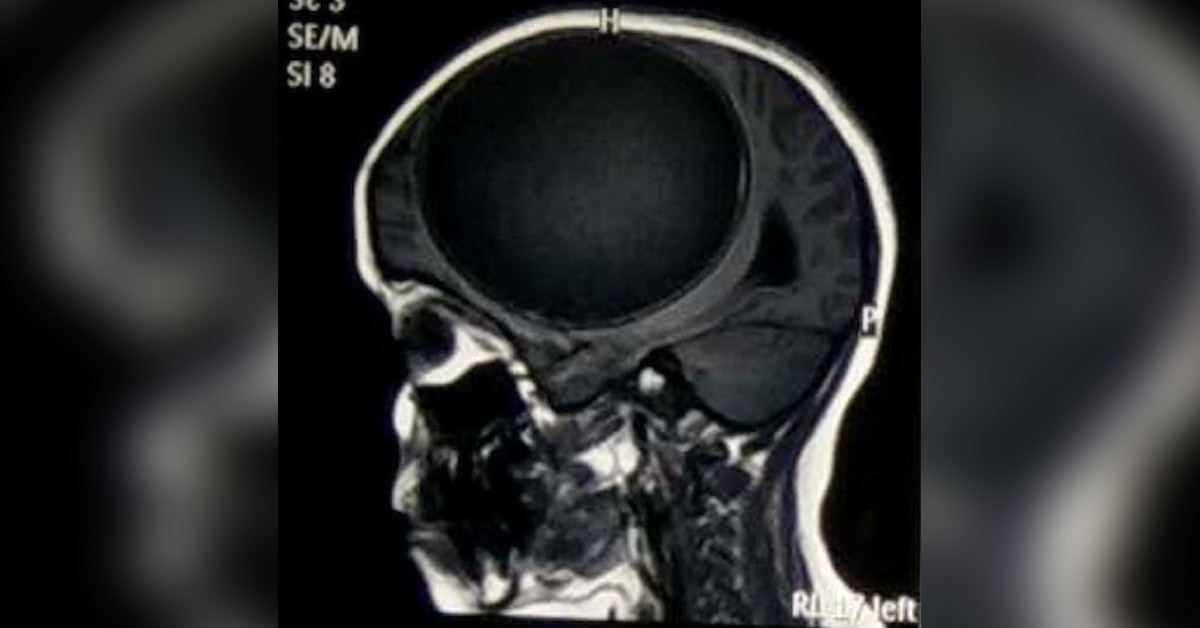

12 yaşındaki Hintli Nita Juggi sürekli nöbet geçiriyor ve son 12 aydır vücudunun bir tarafı felçli haldeydi. Doktora başvurduktan sonra yapılan çeşitli tetkikler sonrasında küçük kızın beyninin yarısını kaplayan Tenya yani bağırsak kurdu larvalarından kaynaklı merkezi sinir sisteminde Sistiserkoz teşhis edildi.

Bir bağırsak kurdunun larvasının sebep olduğu kist greyfurt büyüklüğünde ve her an patlayıp ölüme sebep olabilecek boyutlardaydı. başarılı bir ameliyatla beynindeki kist alınan kız şuan iyileşme sürecinde. Tenya olarak da bilinen bağırsak kurtları parazit bir hayat sürer ve yetişkinlik döneminde bağırsaklarda yaşayarak inanılmaz boyutlara ulaşabilirler. yetişkinlikten önce büyük kistler içerinde bulunan larvalar beyne ulaşabilir ve burada büyümeye devam edebilir.